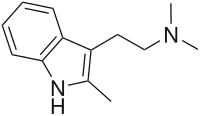

| 2-Methyl-DMT | artificial | 2-CH3 | CH3 | CH3 | (2-(2-methyl-1H-indol-3-yl)-1-methyl-ethyl)dimethylamine | 1080-95-1 |